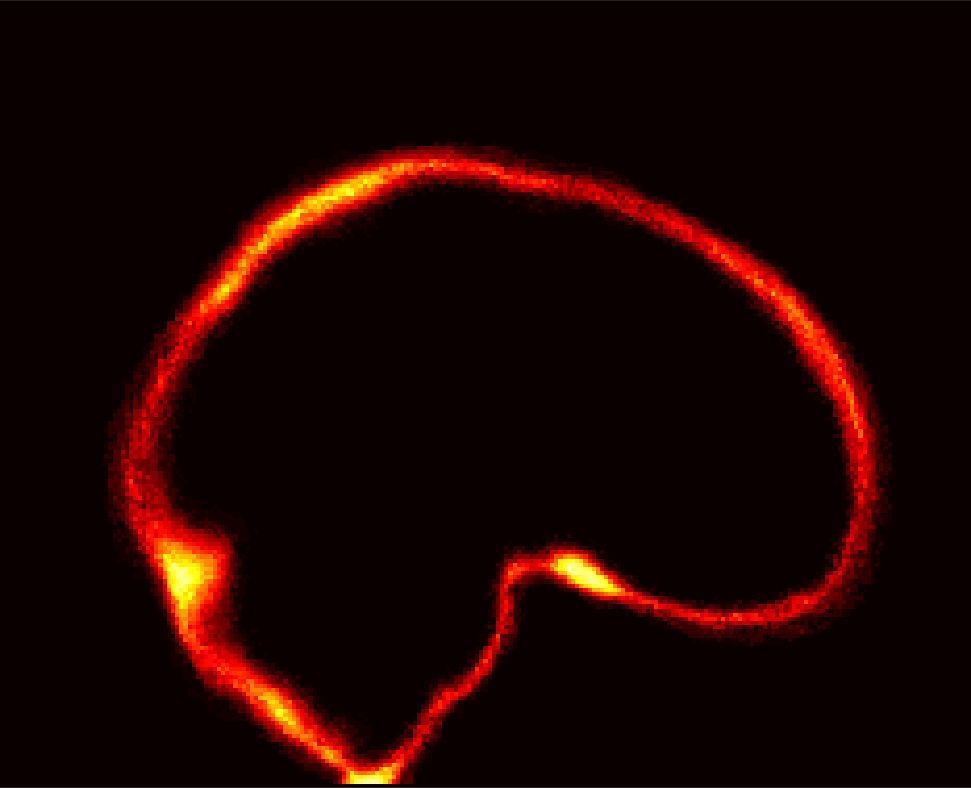

Fig. 1 shows example images from each dataset to illustrate image variability. IBSR and LPBA40 contain images from normal subjects and include large portions of the neck; BRATS has very low out-of-plane resolution; and the TBI dataset contains large pathologies and abnormal skulls.

Refer to caption

Figure 1: Illustration of image appearance variability on a selection of images from each (evaluation) database. From top to bottom: IBSR, LPBA40, BRATS and TBI.